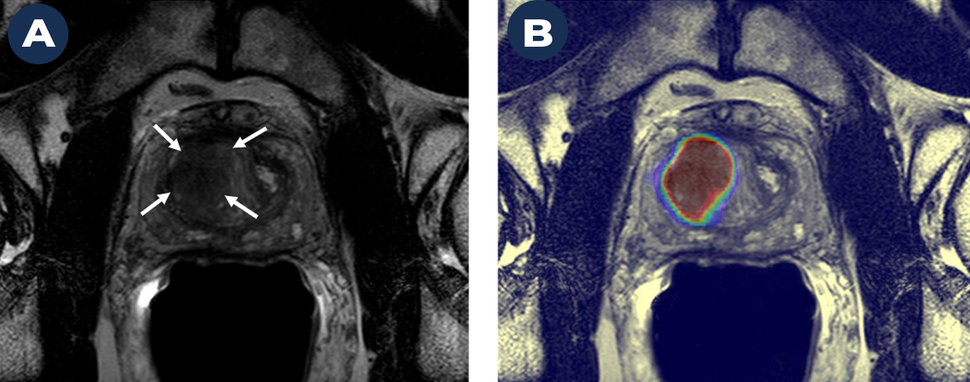

A Magnetic Resonance Image (MRI) on the left (A) shows a suspicious cancer lesion (dark mass marked by arrows). A deep learning-based AI algorithm helps further define this lesion as prostate cancer (B). The lesion in B is displayed as a large red mass, outlined in blue and green. The lesion in B is much larger than the one shown in A, indicating AI helped to better define the extent of the cancer than MRI alone.

We evaluated a patient with a high PSA level (indicating a risk for prostate cancer) and a strong family history of prostate cancer. A Magnetic Resonance Image (MRI) on the left (A) shows a suspicious cancer lesion (marked by arrows). The image on the right (B) shows a high probability of prostate cancer within this lesion based on a deep learning-based AI algorithm. We biopsied the lesion using a technology that “fuses” transrectal ultrasound with MRI and were able to identify the early stages of clinically significant prostate cancer (Gleason 3+4).